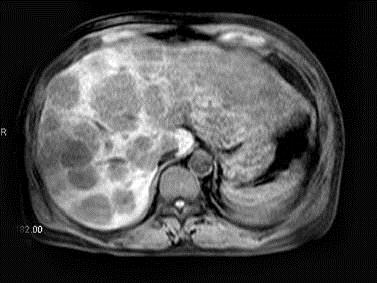

问题 男,58岁,上腹部胀痛不适2月余。MRI见肝内多发病灶。最可能的诊断是()

选项 A.结节型肝癌 B.肝转移瘤 C.肝癌并肝内转移 D.肝硬化并再生结节 E.未见异常

答案 B